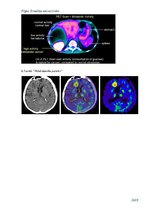

1931.gadā fiziķis Varburgs atklāja, ka ļaundabīgie audzēji patērē lielu glikozes daudzumu. 1977.gadā fiziķis Sokolovs piedāvāja lokāli mērīt glikozes metabolisma līmeni žurku smadzenēs, ievadot žurkas organismā dezoksiglikozi, kas satur radioaktīvu oglekļa izotopu. Savukārt, Felps 1979.gadā piedavajā mērīt to pašu parametru cilvēkiem tikai izmantojot fluordezoksiglikozi, kas satur fluora 18F izotopu. Fluora izotops labāk uzkrājas audos un tam sabrūkot veidojas pozitrons +. Šie atklājumi ir līkuši pamatus mūsdienu pozitronu emisijas tomogrāfu tehnoloģijai, kura ir viena no pasaulē modernākajām un precīzākajām vēža diagnostikas un vēža izplatības pētišanas metodēm.

Dabā pastāv nestabili elementu atomi jeb izotopi, kuriem ir tieksme sabrukties - stabilizēties. Būtībā radioaktīva sabrukšana ir patvaļīga viena ķīmiskā elementa nestabilo izotopu pārvēršanās otra elementa izotopos, vienlaicīgi emitējot elementārdaļiņas vai atomu kodolus. …